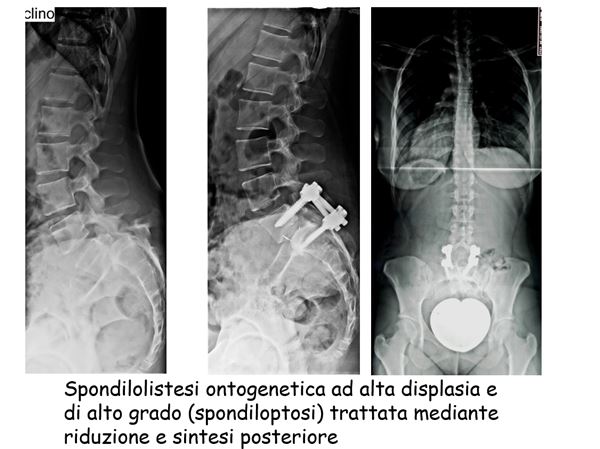

spondilolistesi ontogenetica